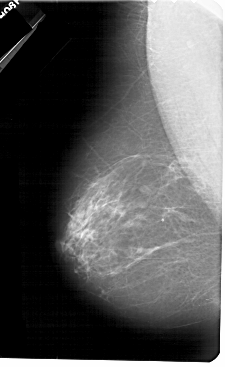

A_1328_1.LEFT_CC

LEFT_CC LINES 5491 PIXELS_PER_LINE 3136 BITS_PER_PIXEL 12 RESOLUTION 43.5 NON_OVERLAY